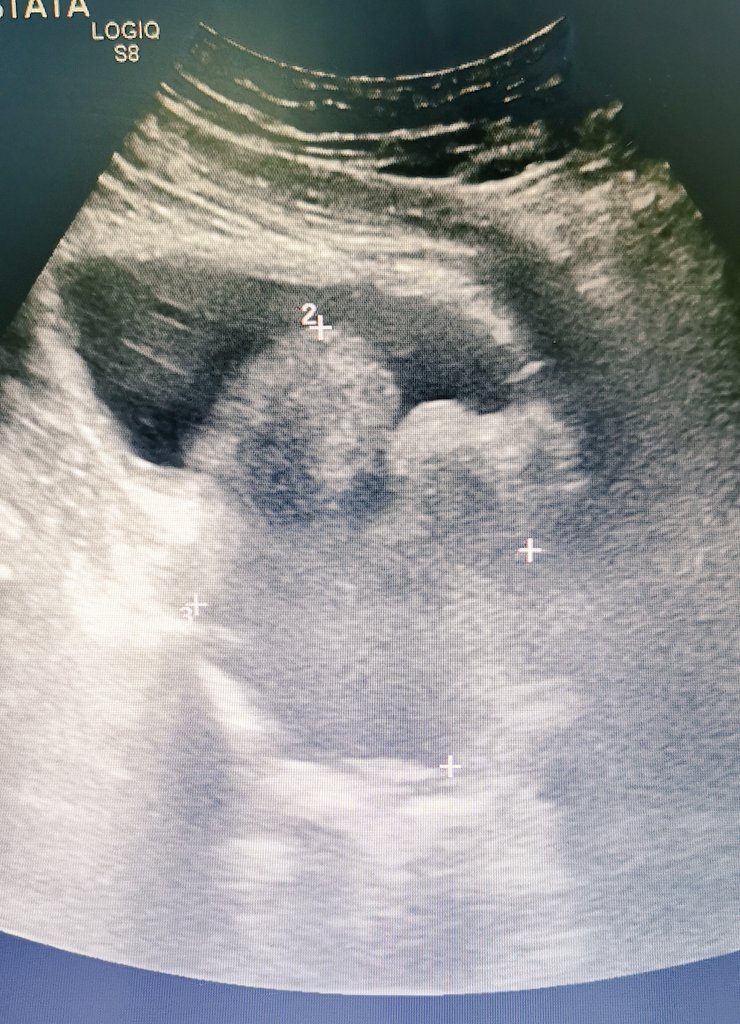

Fem, 65 yrs, ECOG 0, rUTI. US: 4 cm dome bladder tumor Biopsy: Mucinous adenocarcinoma with moderate differentiation, corion invasion. MRI: external iliac LN 15 mm. Next step?

#UroSoMe#urosomebrasil#bladdercancerpic.twitter.com/tPpj8rFBkK